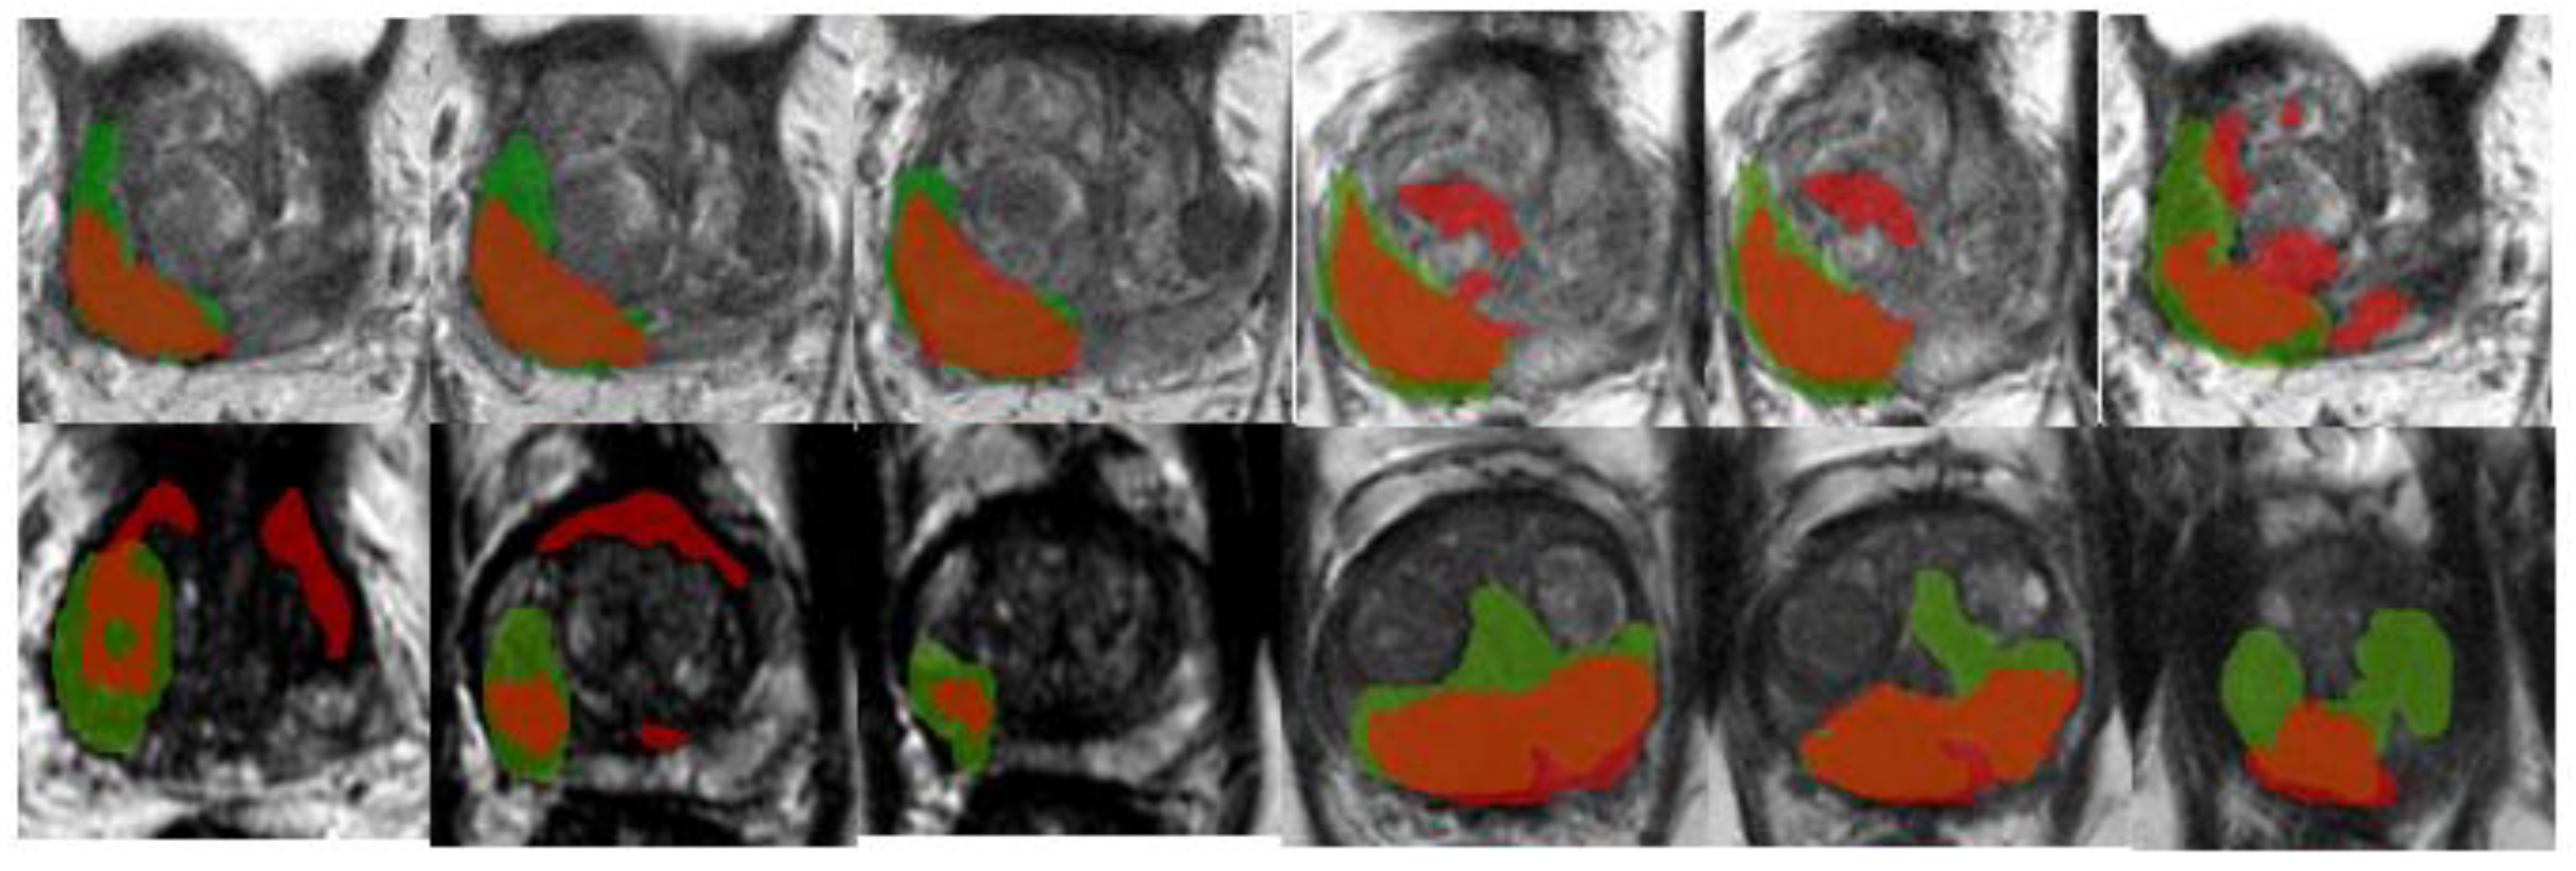

An example of segmentation of cancer foci by the final 3D cancer segmentation model is shown in Figure 18.

Figure 18. Segmentation of cancer by the final 3D segmentation model.